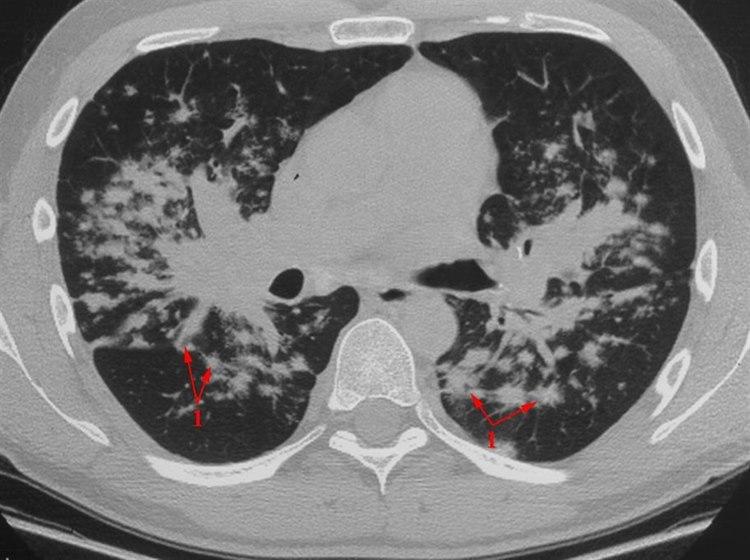

Sarkoidose

HRCT (High resolution CT)

En millimeter tykt CT-snitt

Uregelmessige små knuter (granulomer) med hovedsakelig sentral fordeling